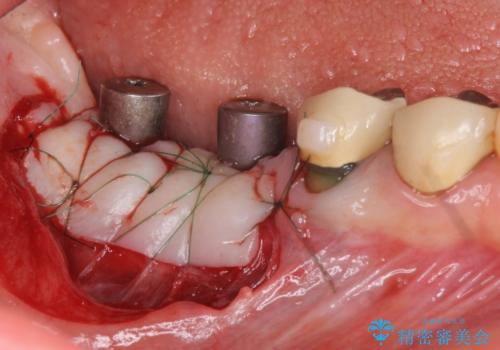

虫歯に伴い歯槽骨の吸収も見られたので造骨後、インプラントを用いて咬合機能を回復します。

また、機能後のインプラント周囲の清掃性を高めるため遊離歯肉移植術を行っています。

インプラント周囲に強固な歯ぐきを移植することで、歯ブラシがしやすくなりインプラント周囲炎対策となります。